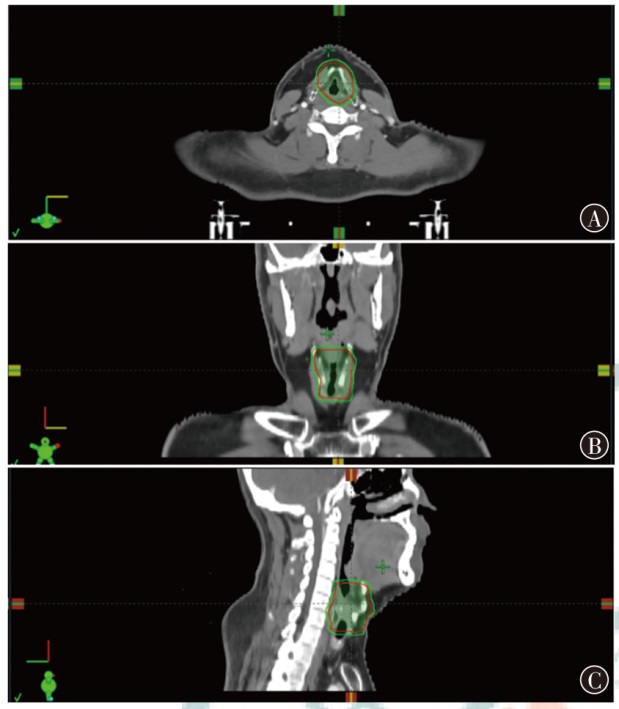

目的探索质子调强放疗(IMPT)和光子容积弧形调强放疗(VMAT)应用于典型头颈部恶性肿瘤的剂量学特点。方法以2023年12月至2024年12月山东省肿瘤防治研究院(山东省肿瘤医院)收治的鼻咽癌、腮腺癌和喉癌患者各1例为研究对象,分别根据靶区和危及器官限值的临床处方要求制定IMPT和VMAT计划。评估3例患者两种计划的靶区适形指数(CI)、均匀性指数(HI)和梯度指数(GI),并评估危及器官的剂量学指标。结果鼻咽癌、腮腺癌和喉癌患者IMPT计划的CI分别为0.70、0.72和0.67,HI分别为0.11、0.08和0.08,GI分别为3.08、2.49和3.75;VMAT计划的CI分别为0.77、0.82和0.91,HI分别为0.12、0.10和0.04,GI分别为3.67、2.63和3.45。IMPT计划的CI略低于VMAT计划,IMPT计划的HI与VMAT计划相当,鼻咽癌和腮腺癌患者IMPT计划的GI低于VMAT计划,喉癌患者IMPT计划的GI高于VMAT计划,且均在临床接受范围。IMPT计划在鼻咽癌、腮腺癌和喉癌治疗中表现出显著的剂量优势:对于鼻咽癌患者,IMPT计划的左、右晶体Dmax比VMAT分别降低了54.1%和50.4%,口腔和喉头的Dmean分别降低了40.5%和49.6%。对于腮腺癌患者,IMPT的脑干和脊髓Dmax比VMAT分别降低了66.2%和40.5%。对于喉癌患者,IMPT的脊髓Dmax比VMAT降低了77.0%,而甲状软骨Dmean比VMAT增加了8.0%。对于患者体内的额外剂量,以患者体内10%、30%和50%的处方剂量区域所占的绝对体积为例,鼻咽癌患者IMPT比VMAT计划分别降低了29.7%、29.6%和34.9%,腮腺癌患者IMPT比VMAT计划分别降低了61.0%、39.7%和17.4%,喉癌患者IMPT比VMAT计划分别降低了63.9%、31.7%和4.1%。结论相比VMAT计划,IMPT计划可有效降低头颈部肿瘤靶区附近大部分危及器官的受照射剂量,但对于紧邻靶区的串型器官,其剂量可能更高,需要引起关注。

ObjectiveTo investigate the dosimetric characteristics of intensity modulated proton therapy (IMPT) and photon volumetric modulated arc therapy (VMAT) in typical head and neck malignant tumors.MethodsThree types of typical head and neck tumors (nasopharyngeal carcinoma, parotid gland carcinoma, laryngeal carcinoma) treated at Shandong Cancer Hospital and Institute from December 2023 to December 2024 were taken as research subjects. IMPT and VMAT radiotherapy plans were created according to clinical prescription requirements of target and organs at risk limits respectively. The conformity index (CI), homogeneity index (HI) and gradient index (GI) for target coverage of two radiotherapy plans were evaluated for 3 patients, as well as the dosimetric indicators of organs at risk.ResultsThe CI of IMPT for nasopharyngeal carcinoma, parotid gland carcinoma and laryngeal carcinoma were 0.70, 0.72 and 0.67, respectively. The HI were 0.11, 0.08 and 0.08, respectively. The GI were 3.08, 2.49 and 3.75, respectively. The CI of VMAT plans were 0.77, 0.82 and 0.91, respectively. The HI were 0.12, 0.10 and 0.04, respectively. The GI were 3.67, 2.63 and 3.45, respectively. The results showed that CI of IMPT plan was slightly lower than that of VMAT plan, and HI of IMPT plan was comparable to that of VMAT plan, the GI of the IMPT plan for patients with nasopharyngeal carcinoma and parotid gland carcinoma was lower than that of the VMAT plan, and the GI of the IMPT plan for patient with laryngeal carcinoma was higher than that of the VMAT plan, and all were within the clinically acceptable range. The IMPT plan has demonstrated significant dose advantages in the treatment of nasopharyngeal carcinoma, parotid gland carcinoma and laryngeal carcinoma. For patient with nasopharyngeal carcinoma, the IMPT plan reduced the Dmaxof the left and right crystals by 54.1% and 50.4%, respectively, compared to VMAT plan, and reduced the Dmeanof the oral and laryngeal tissues by 40.5% and 49.6%, respectively. For patient with parotid gland carcinoma, IMPT plan reduced the Dmaxof the brainstem and spinal cord by 66.2% and 40.5%, respectively, compared to VMAT plan. For patient with laryngeal carcinoma, IMPT reduced spinal cord Dmaxby 77.0%, while thyroid cartilage Dmeanincreased by 8.0% compared to VMAT plan. For the additional dose in the patients' body, taking the absolute volumes occupied by the prescribed dose areas of 10%, 30%, and 50% in the patients' body as examples, IMPT plan of nasopharyngeal carcinoma patient decreased by 29.7%, 29.6%, and 34.9% compared to VMAT plan, respectively. IMPT plan of parotid gland carcinoma patient decreased by 61.0%, 39.7%, and 17.4% compared to VMAT plan, respectively. IMPT plan of laryngeal carcinoma patient decreased by 63.9%, 31.7%, and 4.1% compared to VMAT plan, respectively.ConclusionsCompared with VMAT plan, IMPT plan can effectively reduce the irradiation dose of most organs at risk near the target of head and neck tumors, but the dose of string organs close to the target area may be higher, which needs attention.